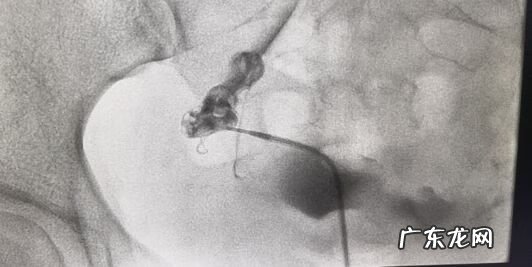

患者 , 32岁 , 顺产女婴2年后 , 未避孕未孕1年 , 外院造影提示右侧输卵管堵塞 , 介入再通治疗后 , 顺产1女 。

文章插图